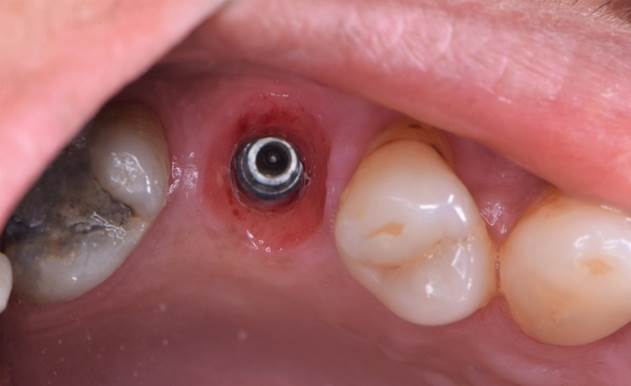

Clinical case: Immediate implant placement using R2GATE Guide & custom healing abutment

- Courtesy of Dr. Sam Omar, Egypt -

Keywords

Dr. Sam Omar, Digital Guided Surgery, Digital ONE-DAY Implant, Maxillary Posterior, #16, Guided surgery, Loading, Flapless, AnyRidge, R2GATE, MEGA ISQ, R2GATE Full surgical kit